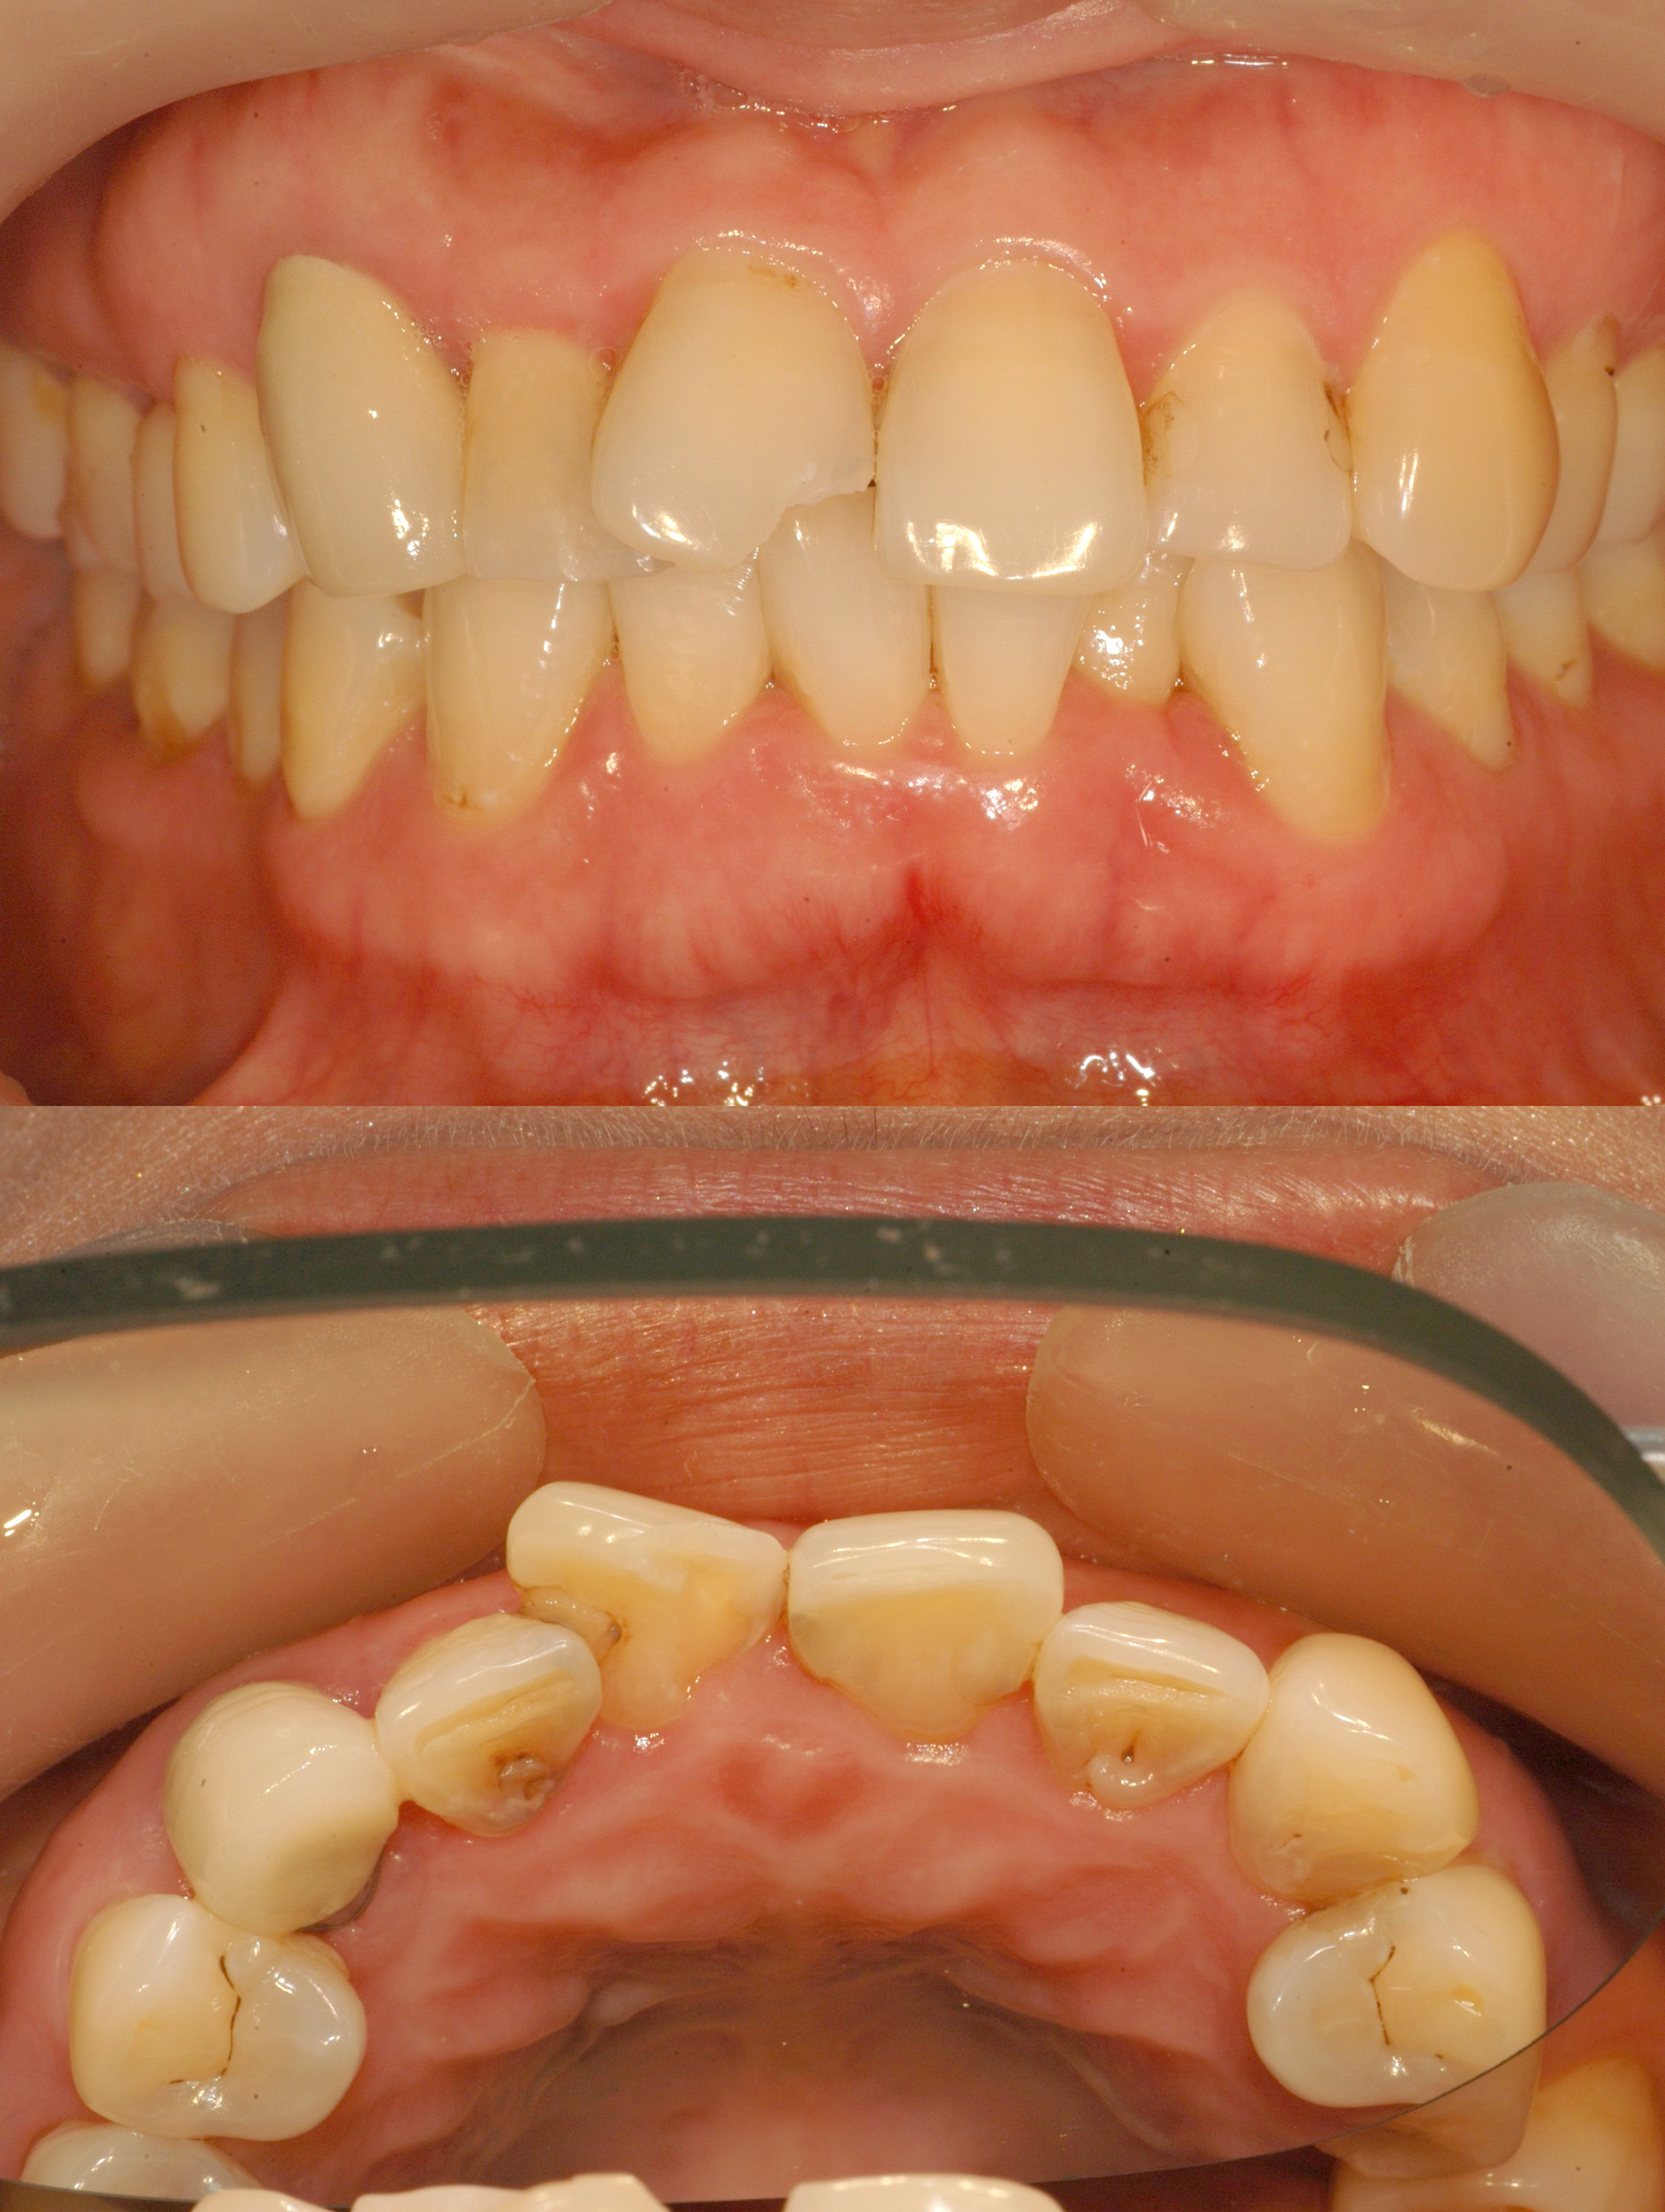

Before & After

> 토브 일반진료 사례

case 01

레진 치료

case 02

인레이 치료

case 03

전악보철

> 토브 협진치료 사례

교정+보철+치은이식

교정+임플란트

Before

라미네이트 시술 전

After

라미네이트 시술 후

올세라믹 크라운 시술 전

올세라믹 크라운 시술 후